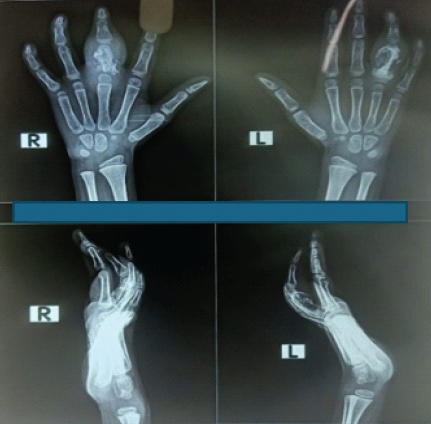

X-rays revealed cystic expansion and cortical thinning [3] of the proximal phalanges with lytic lesions (Fig. 2). Computed tomography imaging confirmed cortical destruction and periosteal reaction (Fig. 3).

Figure 2: X-ray B/L hands showing involvement of phalanx.